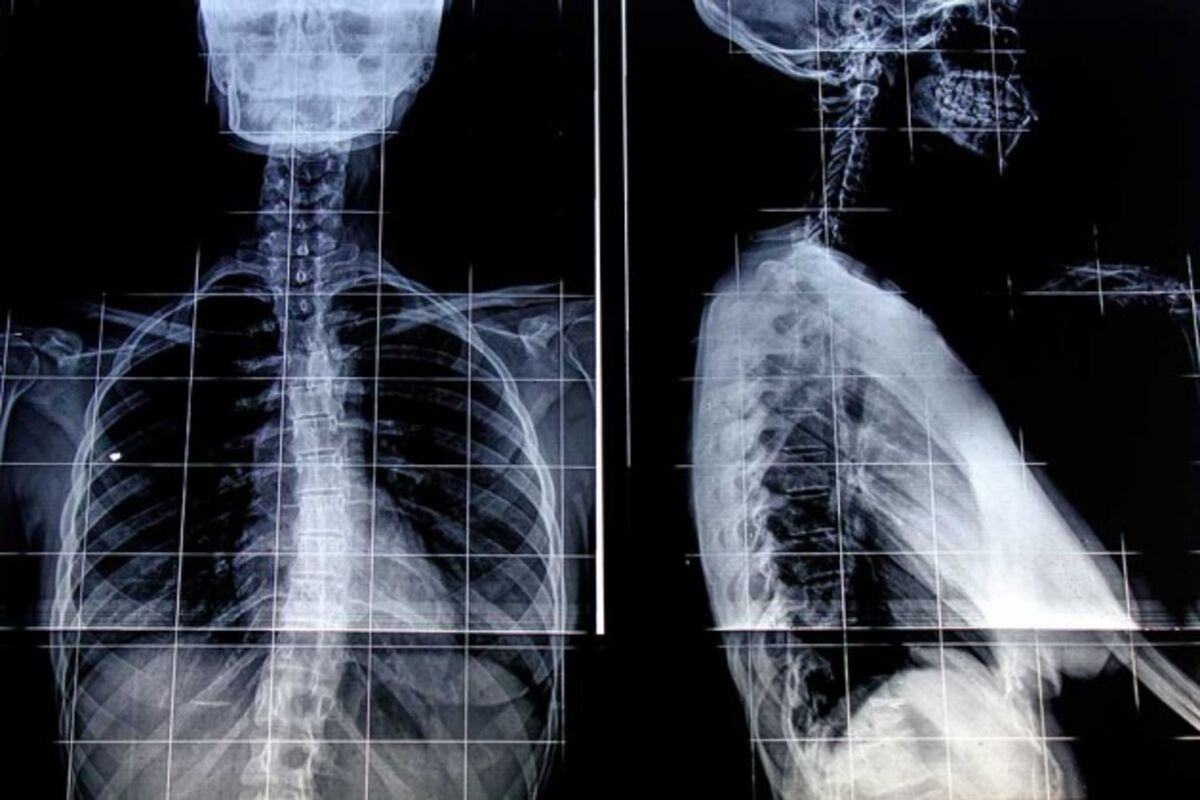

Learning to read a chest x-ray for pneumonia is very important. It can help doctors treat patients quickly and correctly. At Liv Hospital, we use the latest technology and skilled radiologists to find pneumonia accurately. We focus on our patients’ needs.Side-by-side comparison of an x ray of pneumonia vs normal lung image, highlighting key areas of infection.

Chest x-rays are the best way to find community-acquired pneumonia. They show both PA (posteroanterior) and lateral views. This helps doctors understand the lungs better and treat patients right.

X-Ray of Pneumonia vs Normal: Key Differences

Understanding the differences between a normal chest X-ray and one showing pneumonia is key. Pneumonia shows up as white spots in the lungs. These spots are caused by fluid or pus in the air sacs.

Density and Opacity Changes

Pneumonia makes the lung areas look whiter and more solid. This happens because fluid, bacteria, and debris build up in the air sacs. The white spots can be patchy, diffuse, or lobar, depending on the pneumonia type.

Vascular Marking Alterations

In pneumonia, the lung’s blood vessels become harder to see. Normally, these vessels show up clearly. But with pneumonia, the white spots make them less visible.

Air Bronchograms

An air bronchogram is a sign of pneumonia. It happens when the air in the bronchi stands out against the white alveoli. This is because the alveoli are filled with fluid.

Silhouette Sign

The silhouette sign shows when pneumonia makes the lung look like it’s touching nearby structures. This is because the pneumonia makes the lung’s edge blend with the diaphragm or heart. It’s a sign of consolidation.